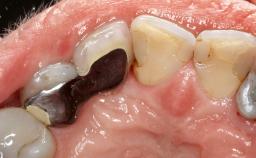

A 70-year-old female patient was referred by her general dentist to the periodontist for assessment and management of an infection associated with implant 36. The general dentist had noted suppuration on probing during examination.